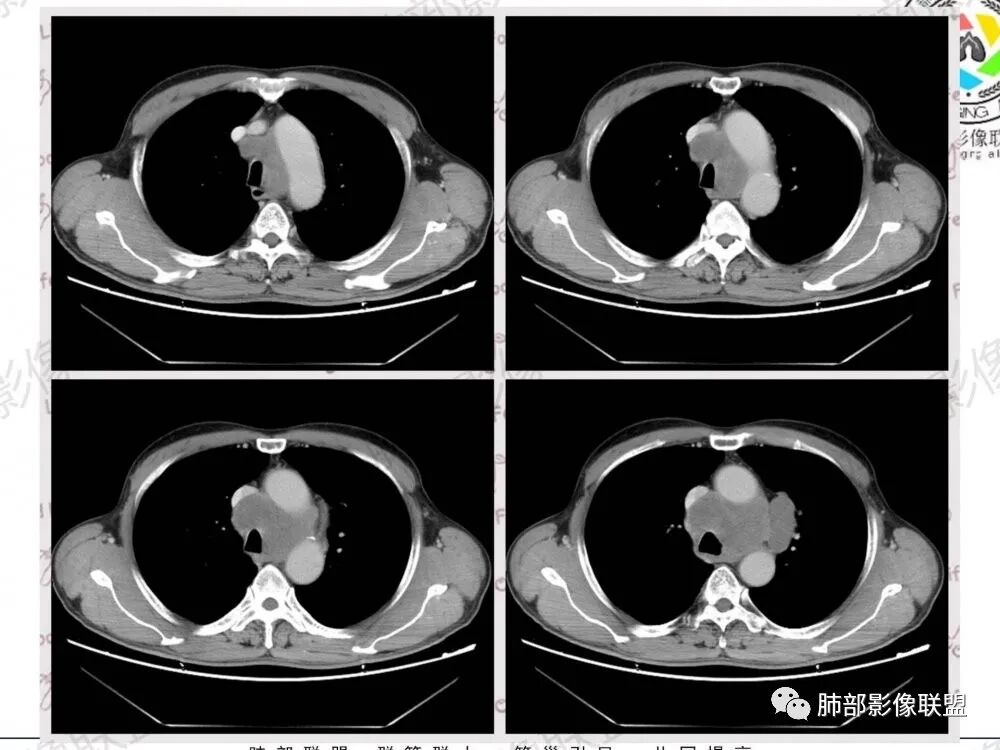

1.左肺门及纵隔见异常增大淋巴结,部分融合,不均匀轻度强化,未见明显坏死。

肿大淋巴结与纵隔血管等结构“无缝”贴合。

2.纵隔增宽但依旧居中。

1.这应当是常见的小细胞肺癌的转移方式。

别忘了,患者左肺上叶那个略显饱满的的小结节,有理由相信那是发源地。

因为这些符合肺癌的整个转移路径!

2、小细胞癌恶性程度高,发展迅速,转移发生早;常有纵隔淋巴结的明显增大融合(发生率达96.5%),呈“冰冻纵隔”,淋巴转移常为逐站的连续性转移;亦有血行转移,脑、肾上腺、肝、胰、骨髓等;转移灶常比原发灶大得多,即“娘小崽大”特点;